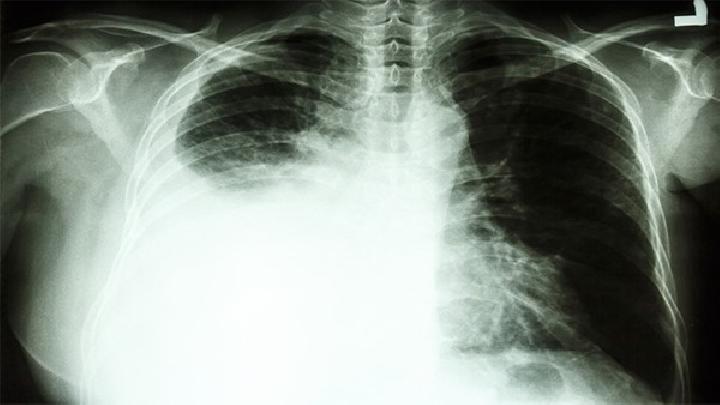

有哪些症状要警惕肺结核

有哪些症状要警惕肺结核?肺结核是现在生活中一种很严重的疾病,而且肺结核威胁到患者的生命健康,所以进行及时的治疗是非常关键的,那么今天我们一起来看看,有哪些症状要警惕肺结核: